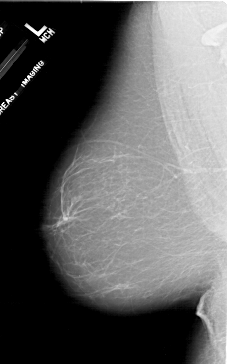

A_1716_1.LEFT_CC

LEFT_CC LINES 6871 PIXELS_PER_LINE 3661 BITS_PER_PIXEL 12 RESOLUTION 43.5 NON_OVERLAY

LEFT_MLO LINES 6541 PIXELS_PER_LINE 4081 BITS_PER_PIXEL 12 RESOLUTION 43.5 NON_OVERLAY